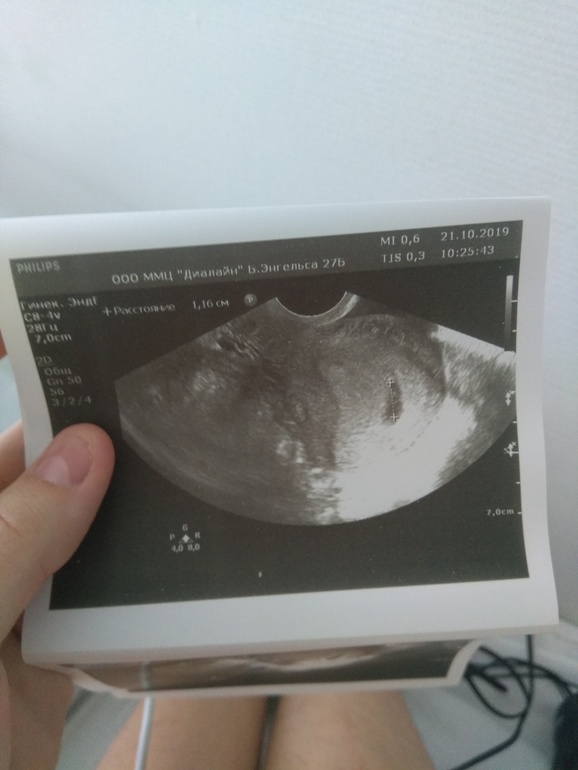

Здравствуйте,девочки подскажите пожалуйста это двойня?Так хочется узнать это 4 неделя былаLUDMILO4KA

у вас в матке 1 пя, значит реб.1.

Может плодное яйцо быть одно а ребенка будет два,это называется близнецы,схожие друг с другом внешне,однояйцевые